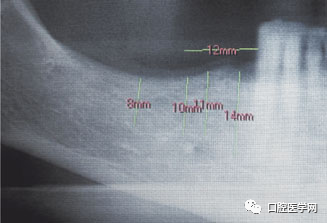

图1 在全景片上进行种植术前设计